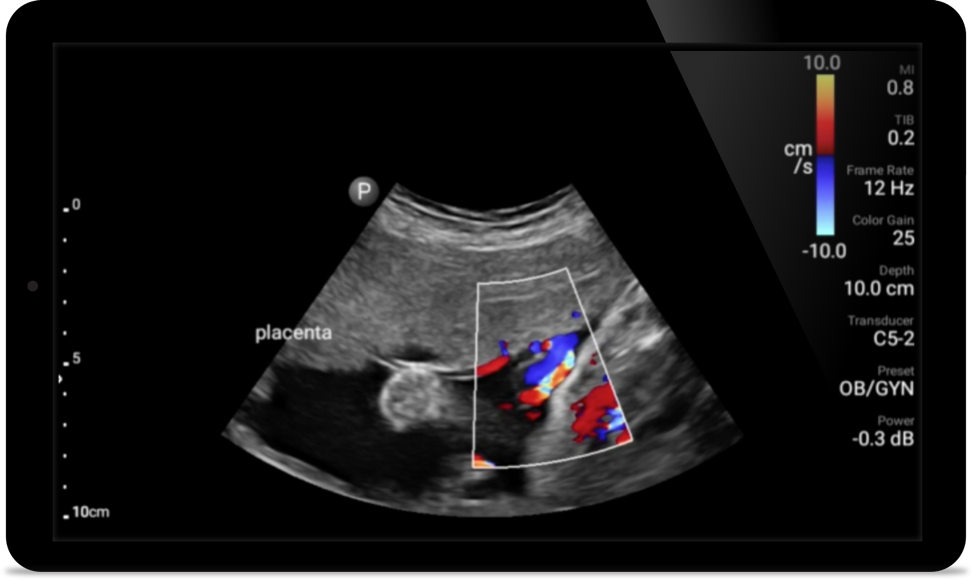

Act faster to protect their heart

When seconds count, portable ultrasound can make the difference. Lumify can provide the high-definition imagery you need whenever and wherever you need it.